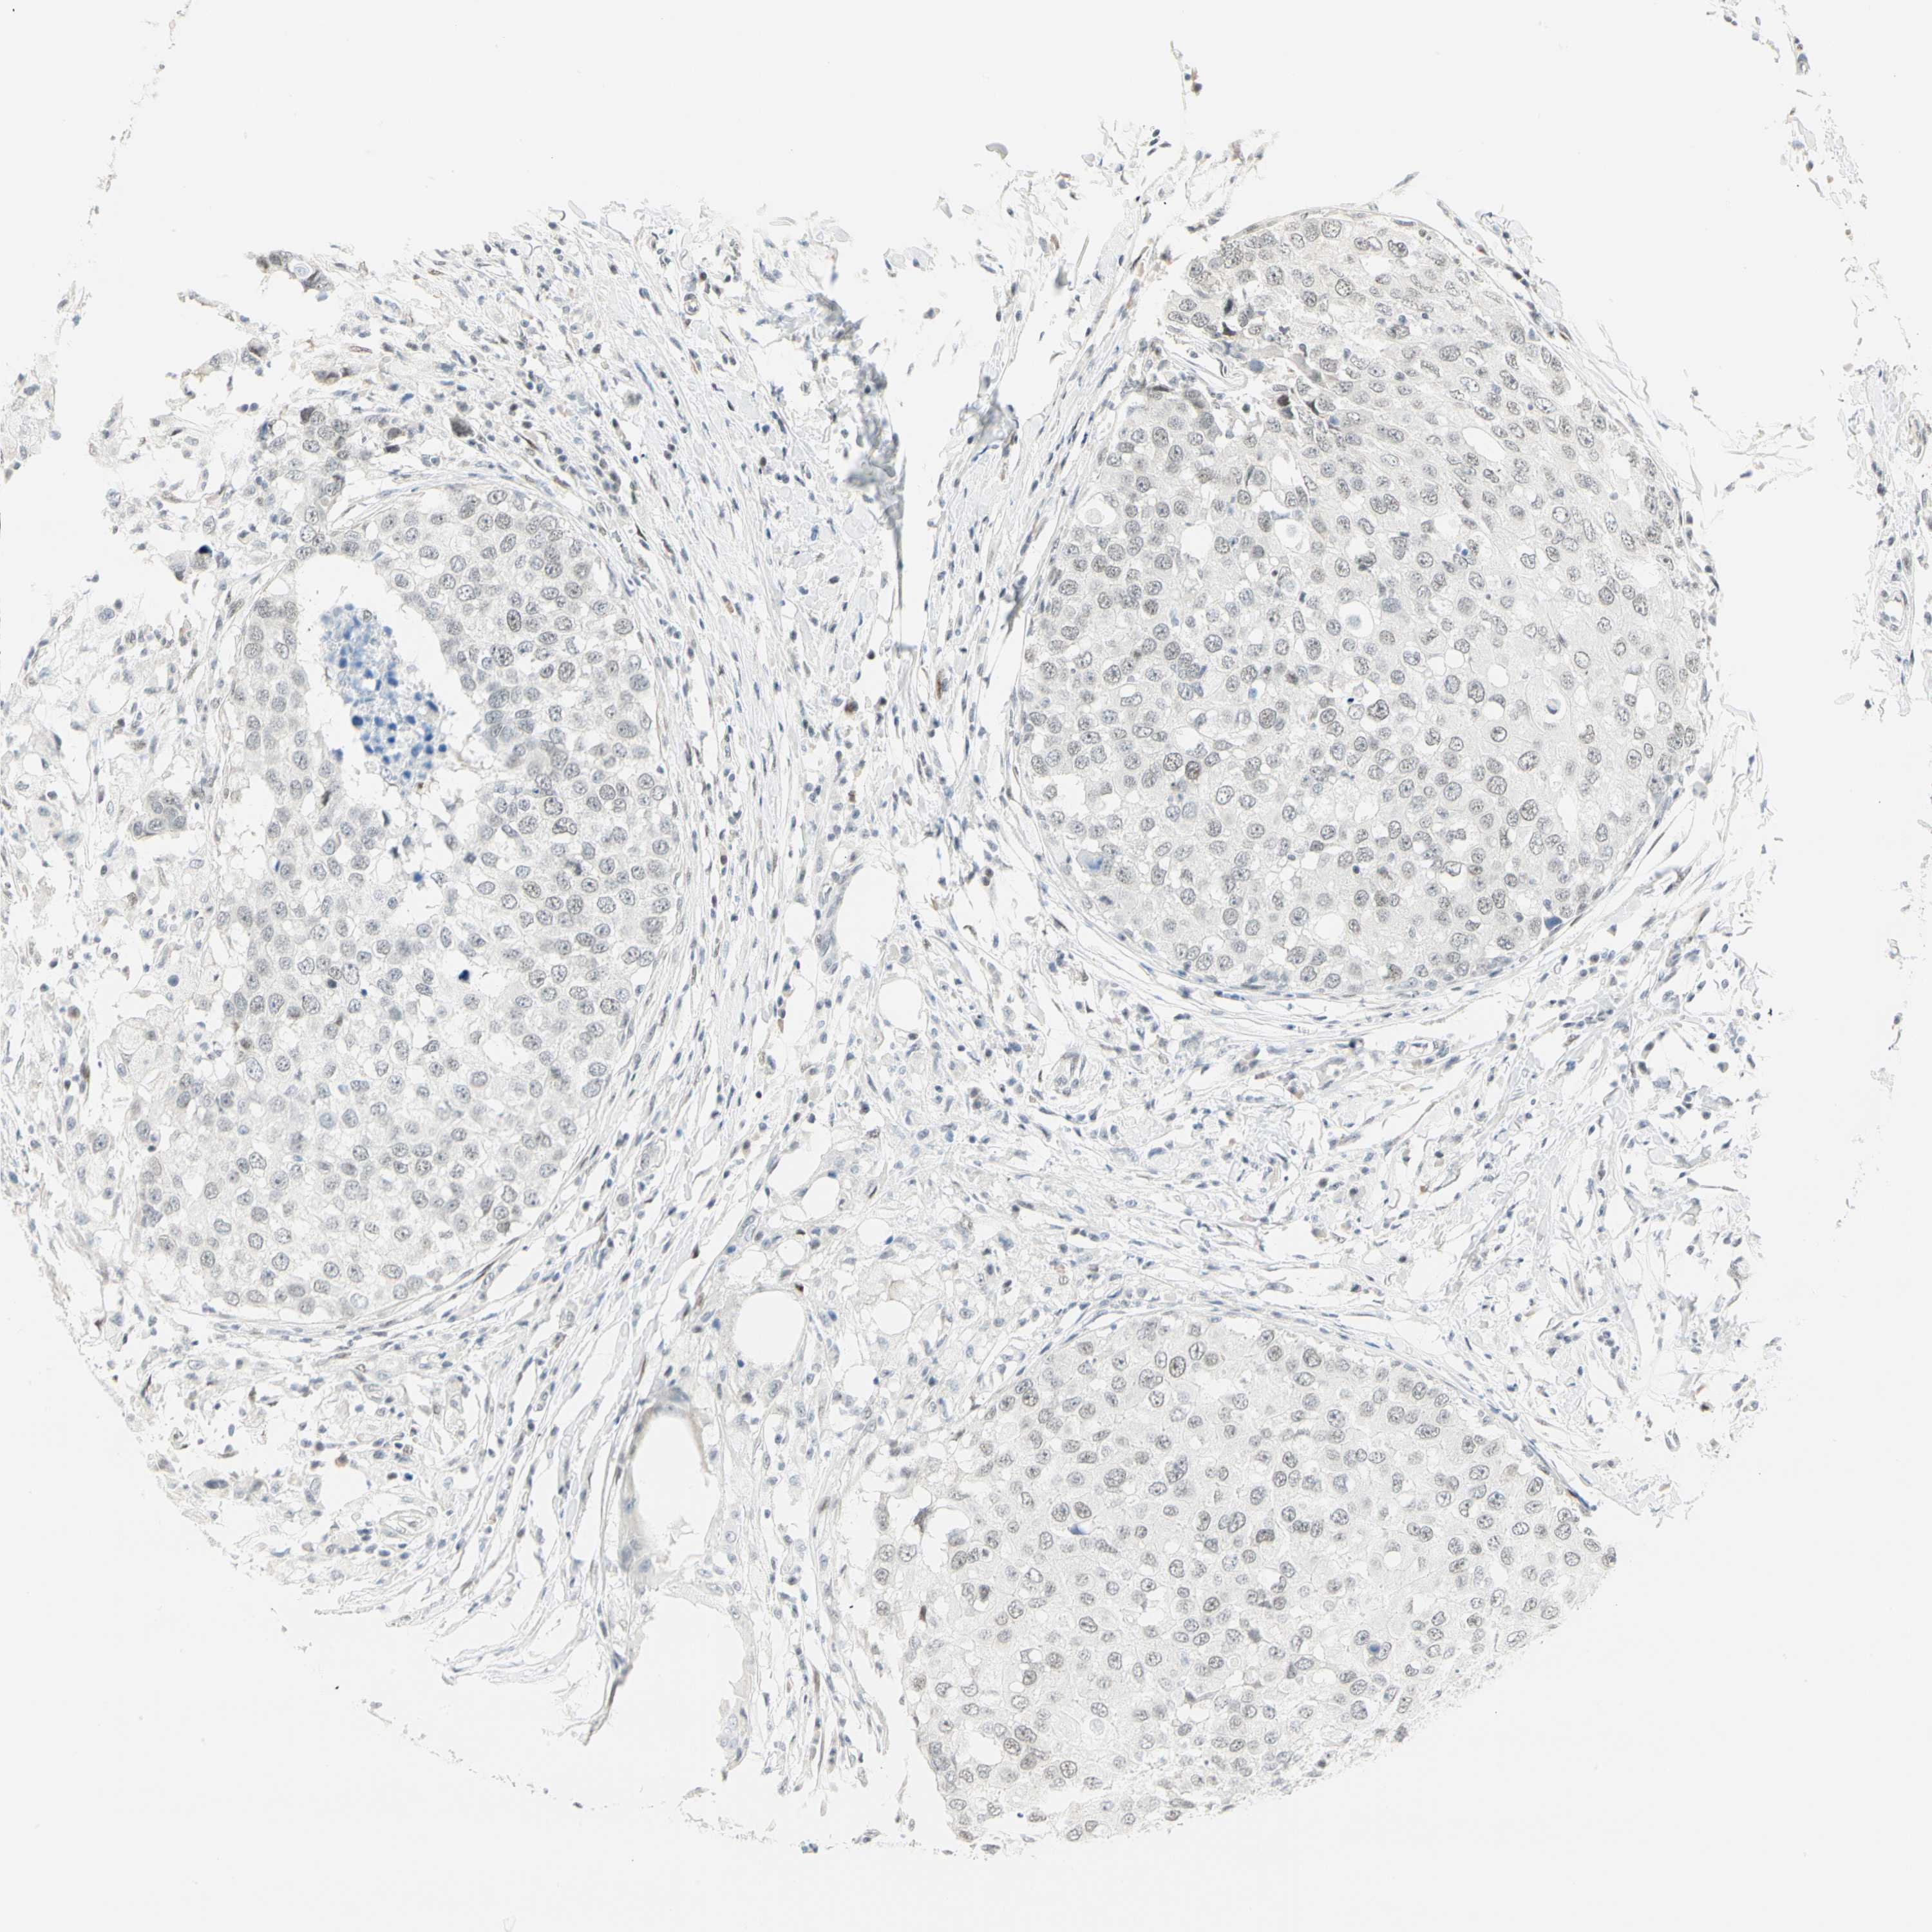

CANCER BREAST CANCER Show tissue menu

BRCA TCGA BRCA VALIDATION PROTEIN EXPRESSION